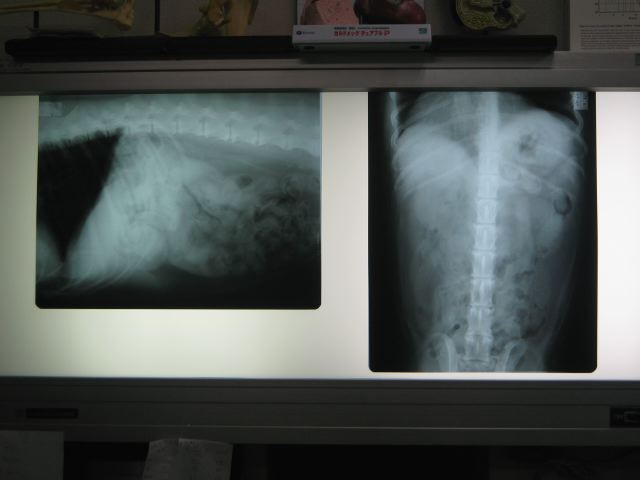

【レントゲン】寛骨?(おしりの骨)近くの腰椎のクッション(椎間板)がなく

なってしまっていて、背骨同士が接触してしまっている。

→これは痛いでしょうとの事。

他に、背骨がトゲ状に変形している箇所もあり(変形性脊椎

症)、ブリッジができかけているところもある。

5枚目はレントゲン。

お尻の骨のあたりの背骨の間がなくて、骨と骨がくっついてしまっているのわかりますかね(^^ゞ

(画像に書き込みができれば良いのですが、できないのです(^^ゞ)